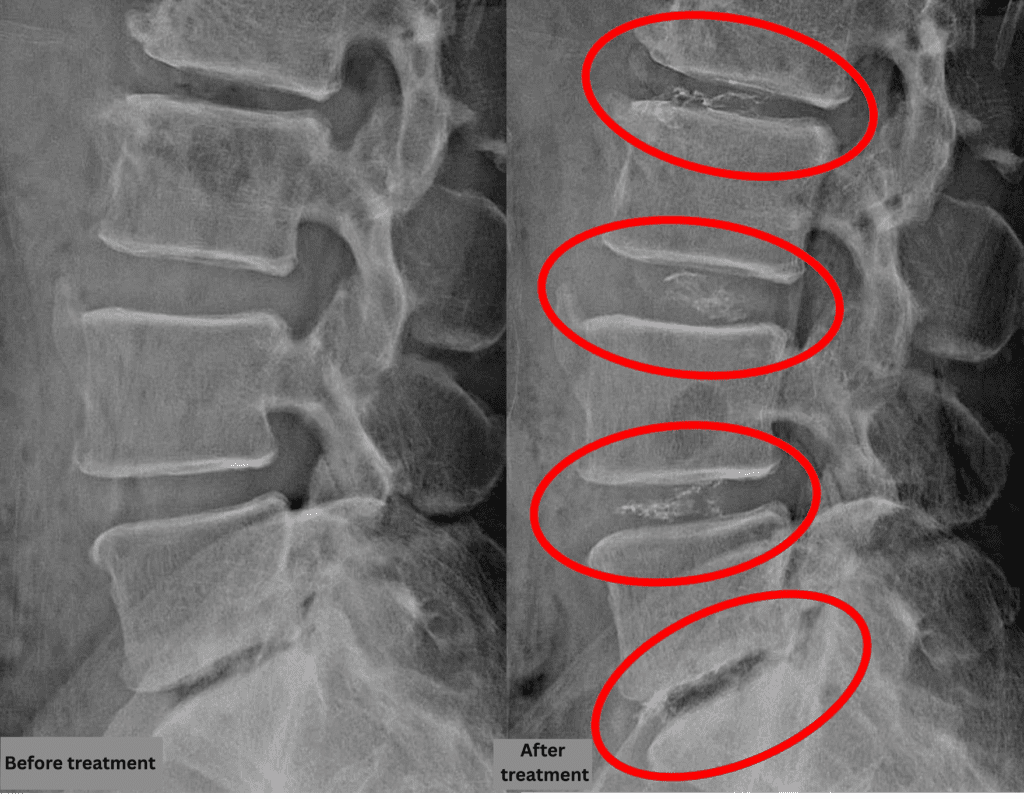

- L1/2: Mild disc degeneration

- L2/3: Disc degeneration, bulging, foraminal stenosis, spinal canal stenosis

- L3/4: Disc degeneration, bulging, foraminal stenosis

- L4/5: Disc degeneration, disc herniation, annular tear

- L5/S: Disc degeneration, disc herniation, endplate degeneration

The above findings were also observed on the imaging.

Compression of the spinal canal and nerve structures due to disc pathology at L2/3, L3/4, L4/5, and L5/S was considered highly likely to be the primary cause of the patient’s symptoms.

After consulting with the patient, the Cellgel Method was performed on L2/3, 3/4, 4/5 and 5/s.